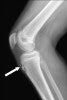

X-ray : 오스굿 슐라터병(Osgood-Schlatter disease, Maid's knee)

초기에는 경골 골절 골단선은 불규칙하게 분리되어 있으나, 말기에는 경골 결절의 세분화가 두드러지게 되며 간혹 슬개건 내에 석회화가 나타나기도 합니다.

한편, 경골 결절이 완전히 떨어진 경우에는 골편이 상방으로 회전 전위되기도 합니다.